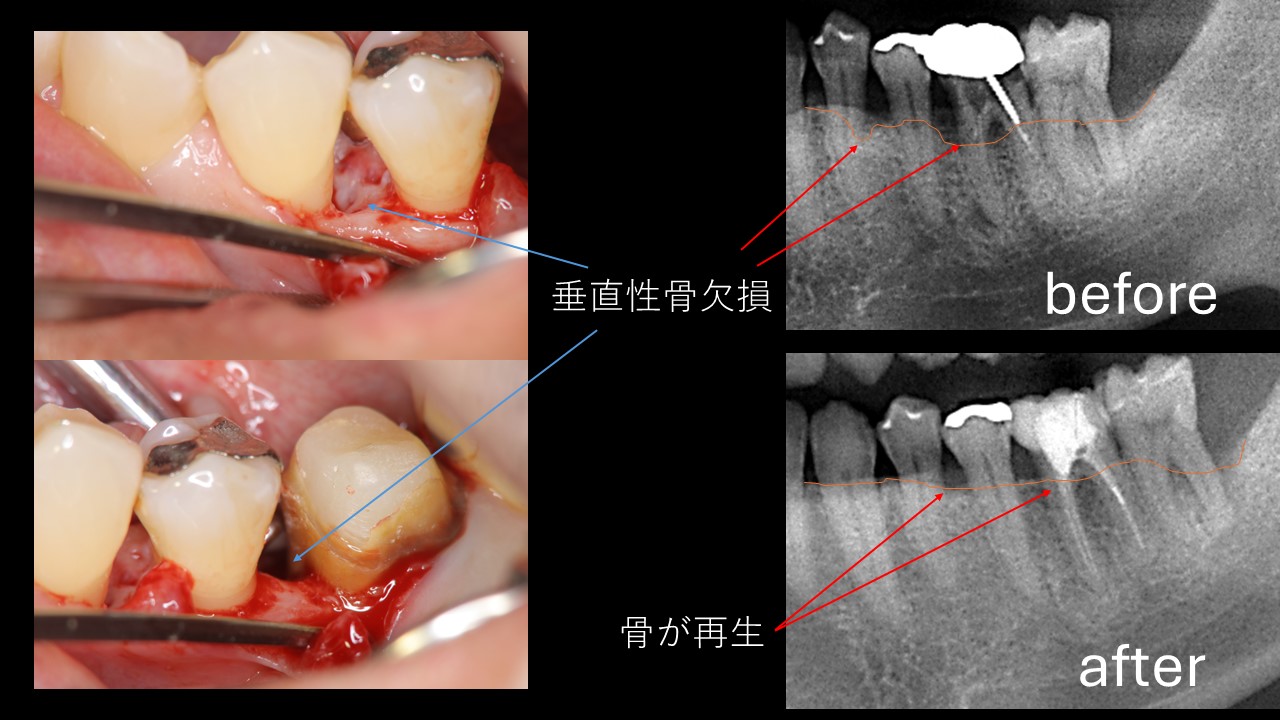

【始めにこちらをお読みください】・本商品は裁断済みです。・スキャン目的のため、1ページずつバラバラの状態になっています。・裁断済みのためやや傷や汚れありのコンディションにしていますが、中のページにつきましては、書き込みや大きな汚れはなく、比較的良好な状態です。・裁断済みであることをご理解のうえ、ご購入をお願いいたします。・裁断済みを理由とした返品はご容赦ください。・まとめ買いご希望の方はお気軽にご申請下さい。低侵襲な手法を用いた歯周組織再生に関する専門書。- タイトル: 低侵襲 歯周組織再生療法- 出版社: クインテッセンス出版定価(本体11,000円+税)ご覧いただきありがとうございます。